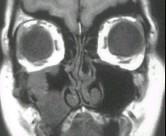

问题 女性,50岁,右鼻塞、脓涕3个月,CT、MRI检查如图所示,请选择正确的答案()

选项 A.右侧上颌窦黏液囊肿 B.右侧上颌窦粘膜下囊肿 C.右侧上颌窦积液 D.右侧上颌窦黏液腺瘤 E.右侧上颌窦腺样囊性癌

答案 E